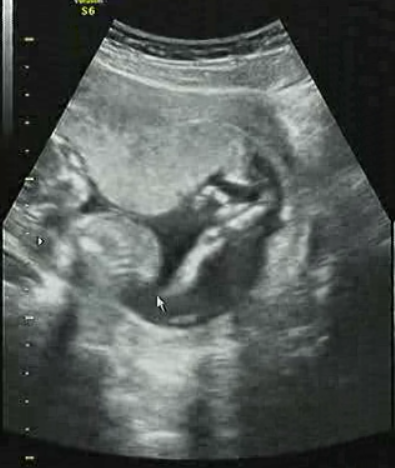

그렇게 생각만 하고 있는 중에도 우리 여름이는

무럭무럭 자라서

한두달 전만해도 점으로도 보이지 않을정도로 작았는데...

아래와 같이 금방 이렇게 컸습니다. ㅎ

8월이면 와이프와 저를 반씩 닮은 아이가 나온다는게

너무 신기하고 어떤 아이일지 너무 궁금하고

설레고 그럽니다. ㅎ